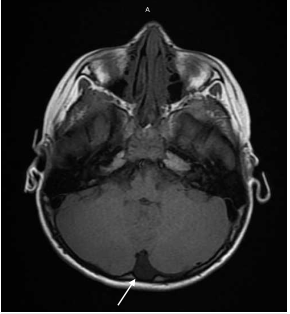

患者因精神状态恶化(AMS)被转移到儿科重症监护室(PICU),在短时间内得到缓解,然后被转移到普通病房接受进一步护理。进行MRI和EEG检查,考虑癫痫活动或颅内病变。MRI显示左侧小脑半球左侧后颅窝有一个小的蛛网膜囊肿(图1)。进一步调查包括氨、促甲状腺激素(TSH)、镁、血沉(ESR)、降钙素原均为阴性。EBV血清学试验也呈阴性。进行唾液毒理学筛查以评估潜在的药物摄入。血清托吡酯水平为3487.8 ng/ml。患者的症状在48小时内消失。根据进一步的询问,发现其母亲使用托吡酯减肥。患儿随后出院,情况稳定。

图1. MRI显示左小脑半球左后窝有一个小的蛛网膜囊肿